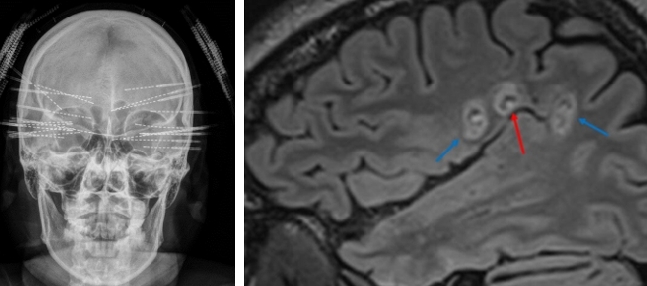

삼차원뇌파(SEEG) 전극은 뇌전증 발생 부위를 정밀하게 확인할 뿐 아니라, 전극을 통해 고주파 열치료(Radiofrequency Ablation, RFA)를 시행할 수 있는 뇌전증 표준 치료 장비다.

고주파 열치료의 효과는 이미 다수의 연구를 통해 입증됐다. 2025년 국제학술지 리뷰 논문(42개 연구, 188명 분석)에 따르면, 약물 난치성 측두엽 뇌전증 환자에게 SEEG 기반 고주파 열치료를 시행한 결과 46.3%에서 발작이 완전히 조절됐으며, 부작용 발생률은 3.8%에 불과했다.